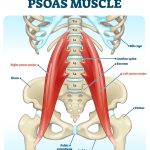

– Mạc cơ tương liên: Fascia của Cơ thắt lưng – chậu (Psoas – Iliacus)

– Thoracolumbar fascia (mạc ngực – thắt lưng): nối Thận – Cột sống – Cơ dựng sống – Cơ chéo bụng)

2- Liên kết cơ – xương – khớp: Cơ liên quan trực tiếp:

– Cơ Psoas Major, Quadratus Lumborum, cơ dựng sống

(Hình ảnh đính kèm: )